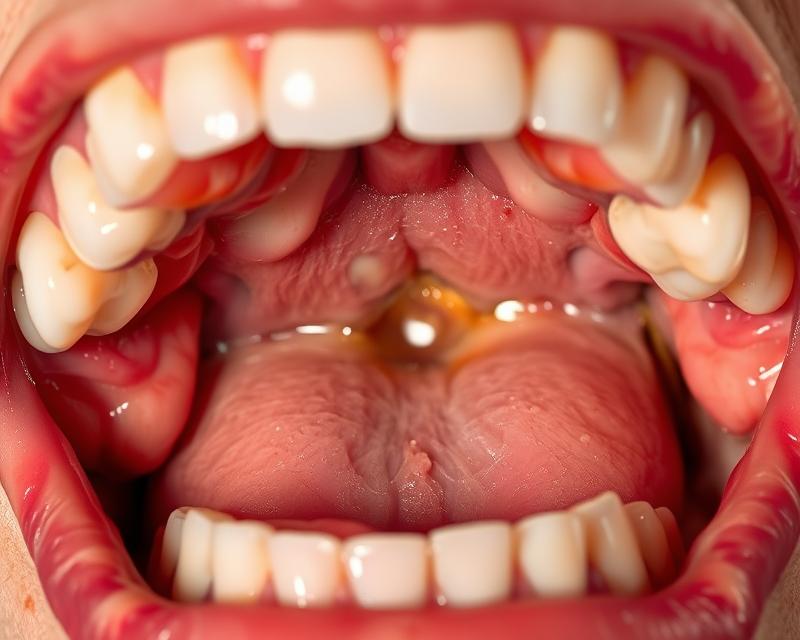

Stany ropne występujące w jamie ustnej to infekcje, które mogą prowadzić do tworzenia ropni w tkankach. Ropień to zbiornik ropy, powstający na skutek zakażenia bakteryjnego. Najczęściej pojawia się w okolicy dziąseł oraz korzeni zębów, ale może również wystąpić w migdałkach czy języku. Zwykle znajduje się w pobliżu miejsca infekcji, takiego jak zakażona kieszonka dziąsłowa lub ząb z martwą miazgą.

Objawy ropnia w jamie ustnej mają różnorodny charakter i występują w zależności od lokalizacji oraz rozmiaru zmiany. Najczęściej pacjenci odczuwają intensywny, pulsujący ból, zwłaszcza podczas dotykania, przełykania śliny czy spożywania jedzenia i napojów. Dodatkowo, obrzęk oraz zaczerwienienie w obrębie dotkniętych miejsc świadczą o toczącej się infekcji.